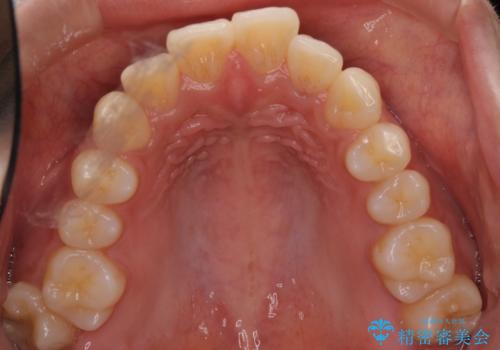

口元の突出感がありと、下顎の前歯が1本欠損していました。

上顎の前から両側の前から4番目の歯と、下あごの前歯を1本抜歯して、口元をすっきりさせる計画としました。

もともと大人の歯が欠損している方はたくさんいます。

その場合、事前の治療計画が重要となります。